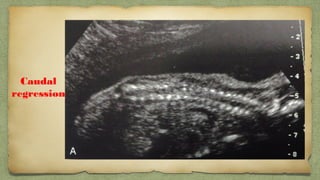

Caudal

regression